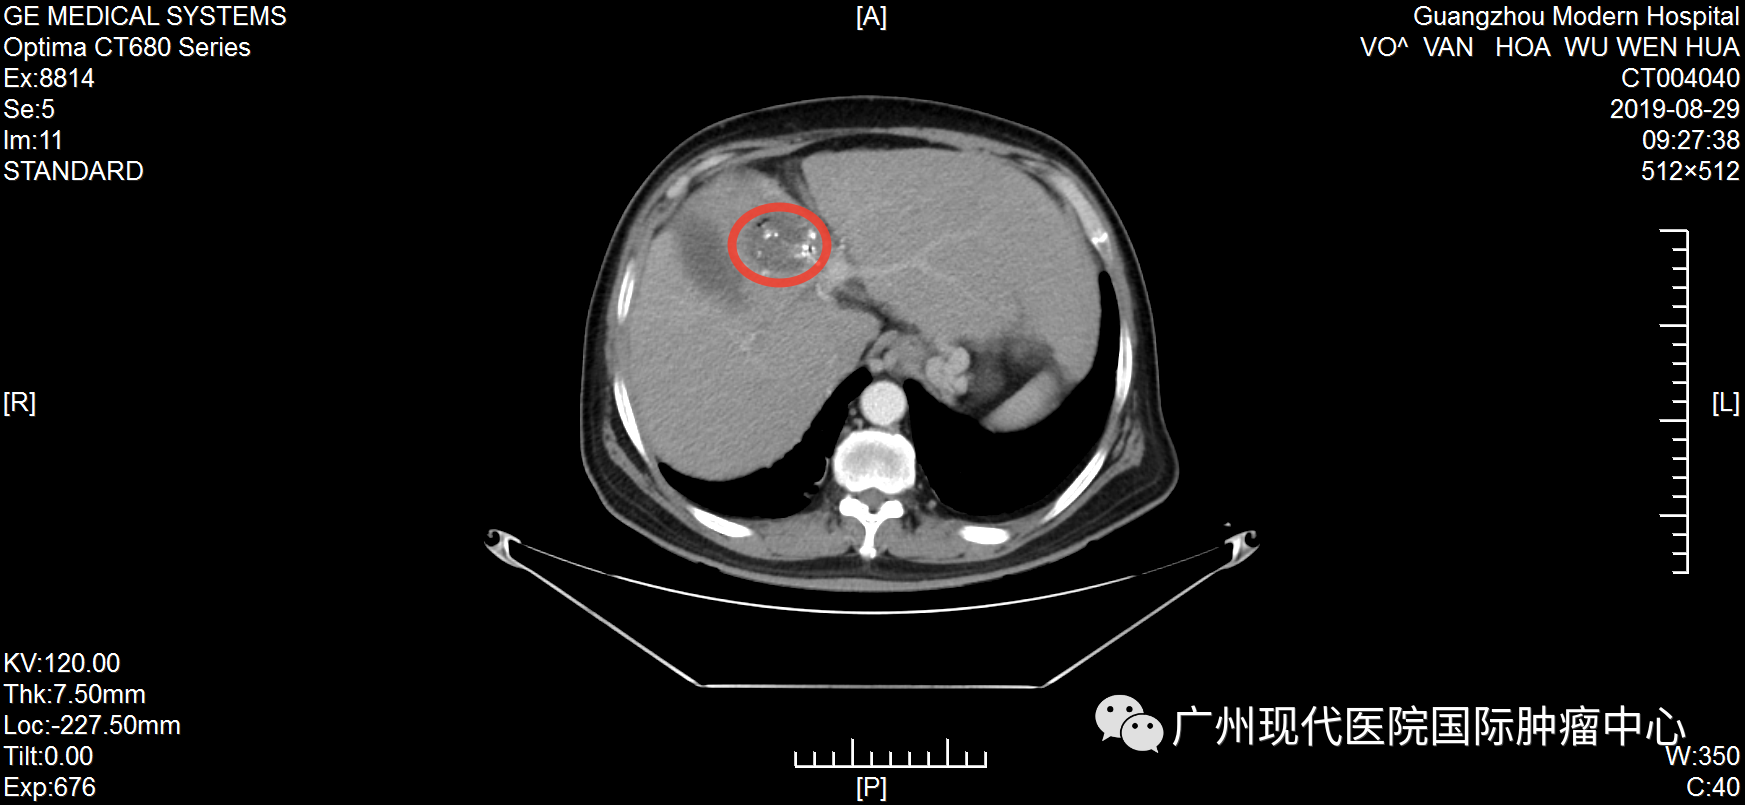

不愿做手術(shù), 弟子推薦好醫(yī)院 武文華自10歲起出家,年輕時,一直去各大佛寺學習佛教知識和游歷,直至1999年時確診丙肝,此后一直堅持吃藥治療。不曾想,時間的指針轉(zhuǎn)到2019年,丙肝惡化為肝癌。 2019年6月,武文華因反復勞累出現(xiàn)低熱,伴隨右上腹脹痛、頭痛等癥狀,且面部神經(jīng)受影響,尤其是下頜與唇部麻痹且疼痛。隨后,他到當?shù)蒯t(yī)院就診,做腹部CT檢查,初步診斷為肝細胞肝癌、肝硬化。當?shù)蒯t(yī)生建議做手術(shù),武先生不愿意開膛破肚,也擔心手術(shù)風險、術(shù)后感染等問題,于是拒絕越南醫(yī)生的治療方案。 武文華和妹妹及弟子合影 機緣巧合下,武文華的弟子了解到自己的一位親友在一家口碑很好的癌癥專科醫(yī)院——圣丹福廣州現(xiàn)代腫瘤醫(yī)院獲得了很好的治療,現(xiàn)在腫瘤已經(jīng)完全消失了。弟子把這家醫(yī)院推薦給武文華,告訴他不用開刀也能很好地治療癌癥,并給他介紹最新的微創(chuàng)技術(shù)?!安挥瞄_刀”這一技術(shù)優(yōu)勢深深地吸引了武文華,他很快找到胡志明辦事處咨詢,并在工作人員的幫助下來到廣州。 微創(chuàng)綜合治療, 讓他重獲新生 2019年7月,武文華來到圣丹福廣州現(xiàn)代腫瘤醫(yī)院。根據(jù)他的病情,醫(yī)院MDT醫(yī)療團隊研討決定,給予他綜合微創(chuàng)治療方案。 第一次住院期間,武文華先后接受介入治療、納米刀等微創(chuàng)治療。介入治療可以切斷癌細胞營養(yǎng)供給,抑制腫瘤生長,減少腫瘤轉(zhuǎn)移,直至徹底殺死腫瘤;而納米刀是一種全新的尖端腫瘤消融技術(shù),通過電極探針釋放高壓脈沖擊穿腫瘤細胞的細胞膜,形成多個納米級不可逆的電穿孔,破壞細胞膜,從而破壞癌細胞組織,使細胞快速凋亡。他曾經(jīng)的主治醫(yī)生馬主任表示,這個治療方案,非常適合武文華這種不愿接受傳統(tǒng)治療、甚至對放化療已經(jīng)產(chǎn)生耐受性的癌癥患者。 2019年武文華住院期間生活照 據(jù)了解,入院前,武文華體內(nèi)的腫瘤大小為70*60mm。經(jīng)介入栓塞治療和納米刀治療后,腫瘤縮小到22*16mm?;貞浿委熯^程,武文華表示:“因為不需要開刀,每一次微創(chuàng)治療都在半小時內(nèi)結(jié)束。做介入治療時,沒有任何痛感,第二天就可以下床。納米刀是在全麻的情況下做的,沒什么感覺?!?/span> 治療1個月后,肝部腫瘤明顯縮小 治療5個月后,腫瘤已基本消失 活動中,馬主任回憶稱:“他總共接受了5次介入治療和納米刀治療,綜合治療完成后,肝部的腫瘤基本消失,他頭痛發(fā)燒及面部神經(jīng)影響等問題也得到了解決?!蹦[瘤消失后,為了鞏固治療效果,他遵守醫(yī)囑再次入院并接受了免疫治療。 自2019年7月至今,武文華已經(jīng)抗癌成功5年了,這對于他的家人而言是一種莫大的幸福。他的妹妹欣喜地說:“此前在越南的醫(yī)院,醫(yī)生下結(jié)論說他不做手術(shù)只能活3個月,如果做手術(shù)成功率只有30%。時間證明我們選擇來廣州治療是對的,現(xiàn)在他每年仍然在越南定期檢查,結(jié)果完全穩(wěn)定,而健康的狀態(tài)現(xiàn)在已經(jīng)延長了5年,這是一個奇跡!” 醫(yī)患情暖人心, 定下十年之約 這是武文華第三次回到醫(yī)院。在采訪中,他表示:“我完成治療返回越南后,新冠疫情就爆發(fā)了,我像往常一樣進行寺廟的日常管理工作,還積極參加抗疫的工作,我很幸運能夠那么快地恢復健康,這要歸功于醫(yī)院的精心治療和護理。” 住院期間,因為面部神經(jīng)不適等癥狀,武文華被我院醫(yī)護人員悉心照料照顧,他為之動容并為他們創(chuàng)作了一首詩:“別時合影它日憶,此處高風妙可夸。天使殷勤通晝夜,良醫(yī)吐哺映蓮花。”談起寫詩的初衷,他說:“我曾經(jīng)在別的醫(yī)院治療過,后面依然選擇這里,是因為這里的醫(yī)生和護士都非常專業(yè),對病人熱情而周到?!?/span> 2019年,武文華出院時為我院賦詩及合影 活動中,武文華和主治醫(yī)生馬主任合影 他以親身經(jīng)歷,對其他患者強調(diào),腫瘤不是一種絕對導致死亡的疾病,而是一種慢性病。“現(xiàn)在我能夠正常地飲食,工作,還能進行體育鍛煉。如果你確診了癌癥,請不要灰心,不要悲傷,一定要遵守醫(yī)囑,相信自己可以恢復健康。” 抗癌明星的聚會中,馬主任仔細聆聽他的分享,不斷綻放出感動與欣慰交織的笑容。她難掩心潮澎湃,還定下一場“十年之約”:“看到武大師目前擁有這么健康的狀態(tài),我感到我們醫(yī)護人員所有的努力和付出都是值得的。希望十年后和大家再相聚!” 活動后,武文華還同其他抗癌明星們一起,體驗了一場精彩紛呈的廣州之旅。他們夜游珠江,體驗現(xiàn)代都市的繁華;結(jié)伴同游寶墨園,觀中華文化的博大精深。他們的癌后余生,正如腳下的路,徐徐綿延向前,充滿陽光! 微創(chuàng)治療技術(shù)簡介 納米刀:是一種全新的腫瘤消融技術(shù),源于不可逆電穿孔技術(shù),通過電極探針釋放高壓脈沖擊穿腫瘤細胞的細胞膜,形成多個納米級不可逆電穿孔,破壞細胞內(nèi)外平衡,使細胞快速凋亡。治療優(yōu)勢是時間短、 治療區(qū)域的血管、神經(jīng)等重要組織得以保留、安全可靠等。 1、具備創(chuàng)傷小、并發(fā)癥少、安全、恢復快的優(yōu)勢。 2、可適應更多復雜的病情,包括胰腺、肝、肺、腎、前列腺以及其他實體腫瘤 介入治療:在醫(yī)學影像設備引導下穿刺,利用特制導絲等精密器械,將比靜脈點滴藥物濃度高2~8倍的抗腫瘤藥物直接注入腫瘤內(nèi)部,同時對腫瘤的供血動脈進行栓塞,實現(xiàn)腫瘤縮小甚至消失的目的。 1、具備創(chuàng)傷小、并發(fā)癥少、安全、恢復快的優(yōu)勢。 2、適合采用傳統(tǒng)放化療效果不佳、不愿或不適合做手術(shù)等情況的患者。